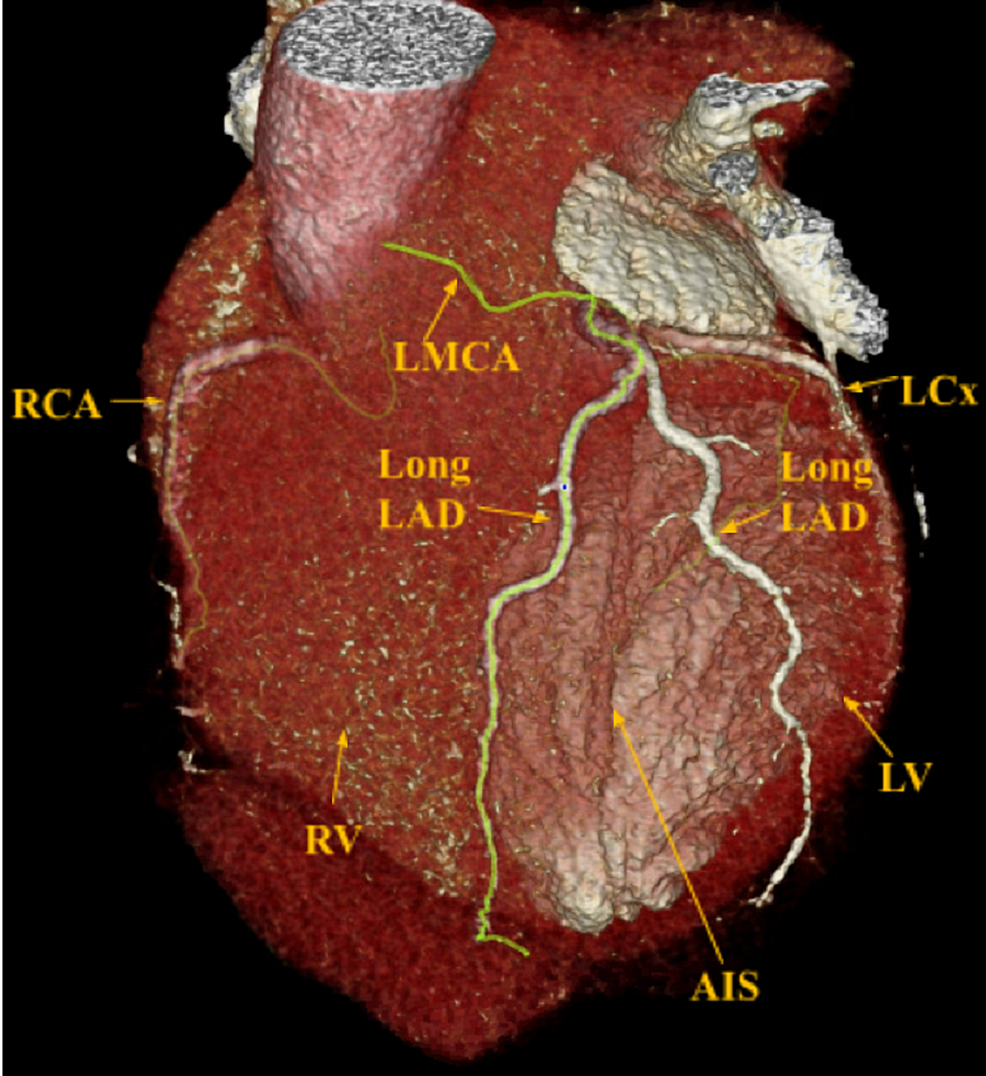

Physiology of Coronary Blood Flow | Radiology Key

Cureus | “Two for One”, Novel Dual Left Anterior Descending Artery (LAD …

Atherosclerotic plaque in left anterior descending artery | Download …

Plaque characteristics of coronary artery on CCTA. Multiplanar …

Coronary CT Angiography in Coronary Artery Disease: Correlation between …